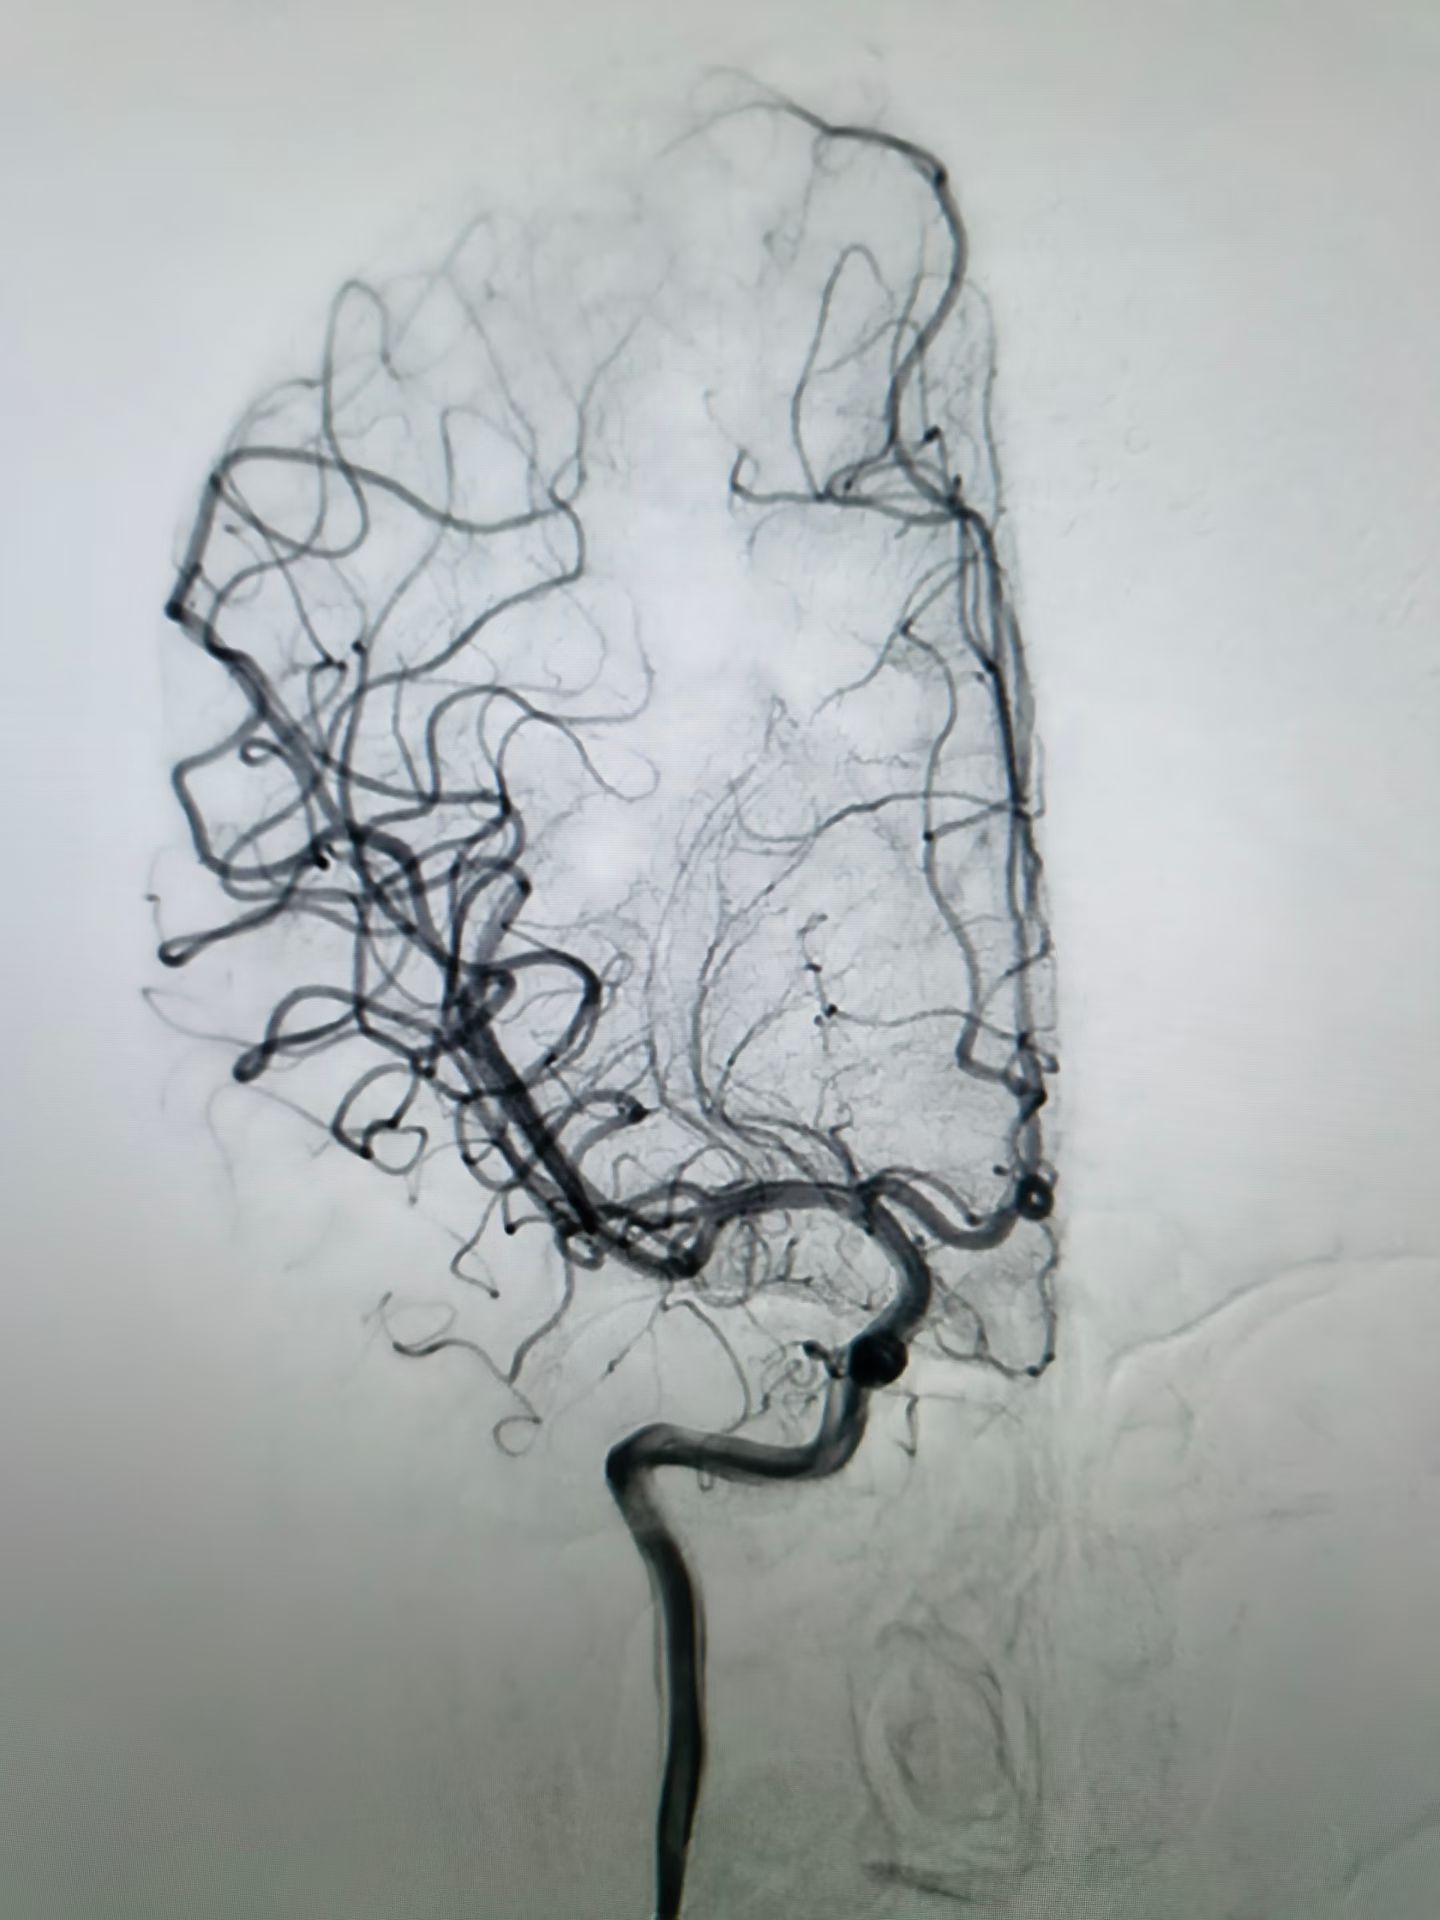

接诊医生凭借丰富的临床经验,高度怀疑急性脑卒中。在完善头颅CT等相关检查后,确诊为急性缺血性卒中,并第一时间启动卒中绿色通道救治流程,由绿色通道送入介入医学科。此时,脑病科主任刘金城、医生任浩及介入医学科团队迅速进行脑血管造影,造影结果提示,其右侧大脑中血管闭塞。治疗团队立即实施机械取栓术,成功将堵塞血管的血栓完整取出。血栓取出后,小李瘫痪的肢体即刻能够抬起。目前小李生命体征稳定,正在恢复中。